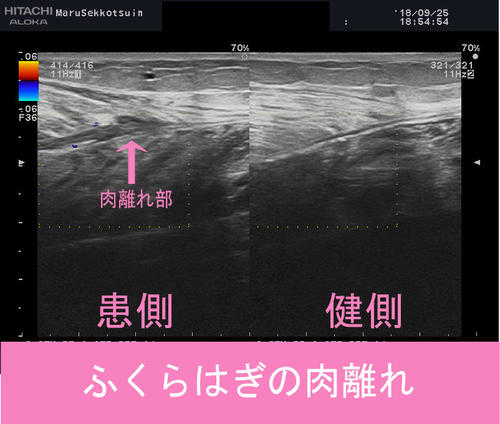

しっかり問診、触診をして、負傷箇所を確定し、深さ・広さを確認する為にエコー検査。

結果、ふくらはぎ肉離れ、好発部位である「腓腹筋内側頭部の肉離れ」でございました。

calf2.jpgcalf.jpg